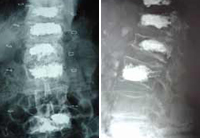

![]() Cifoplastia de L2 |

Cifoplastia con balón en cinco niveles realizada por el Dr. Morgenstern. La paciente es una mujer de 80 años, deambulación erecta inmediata |